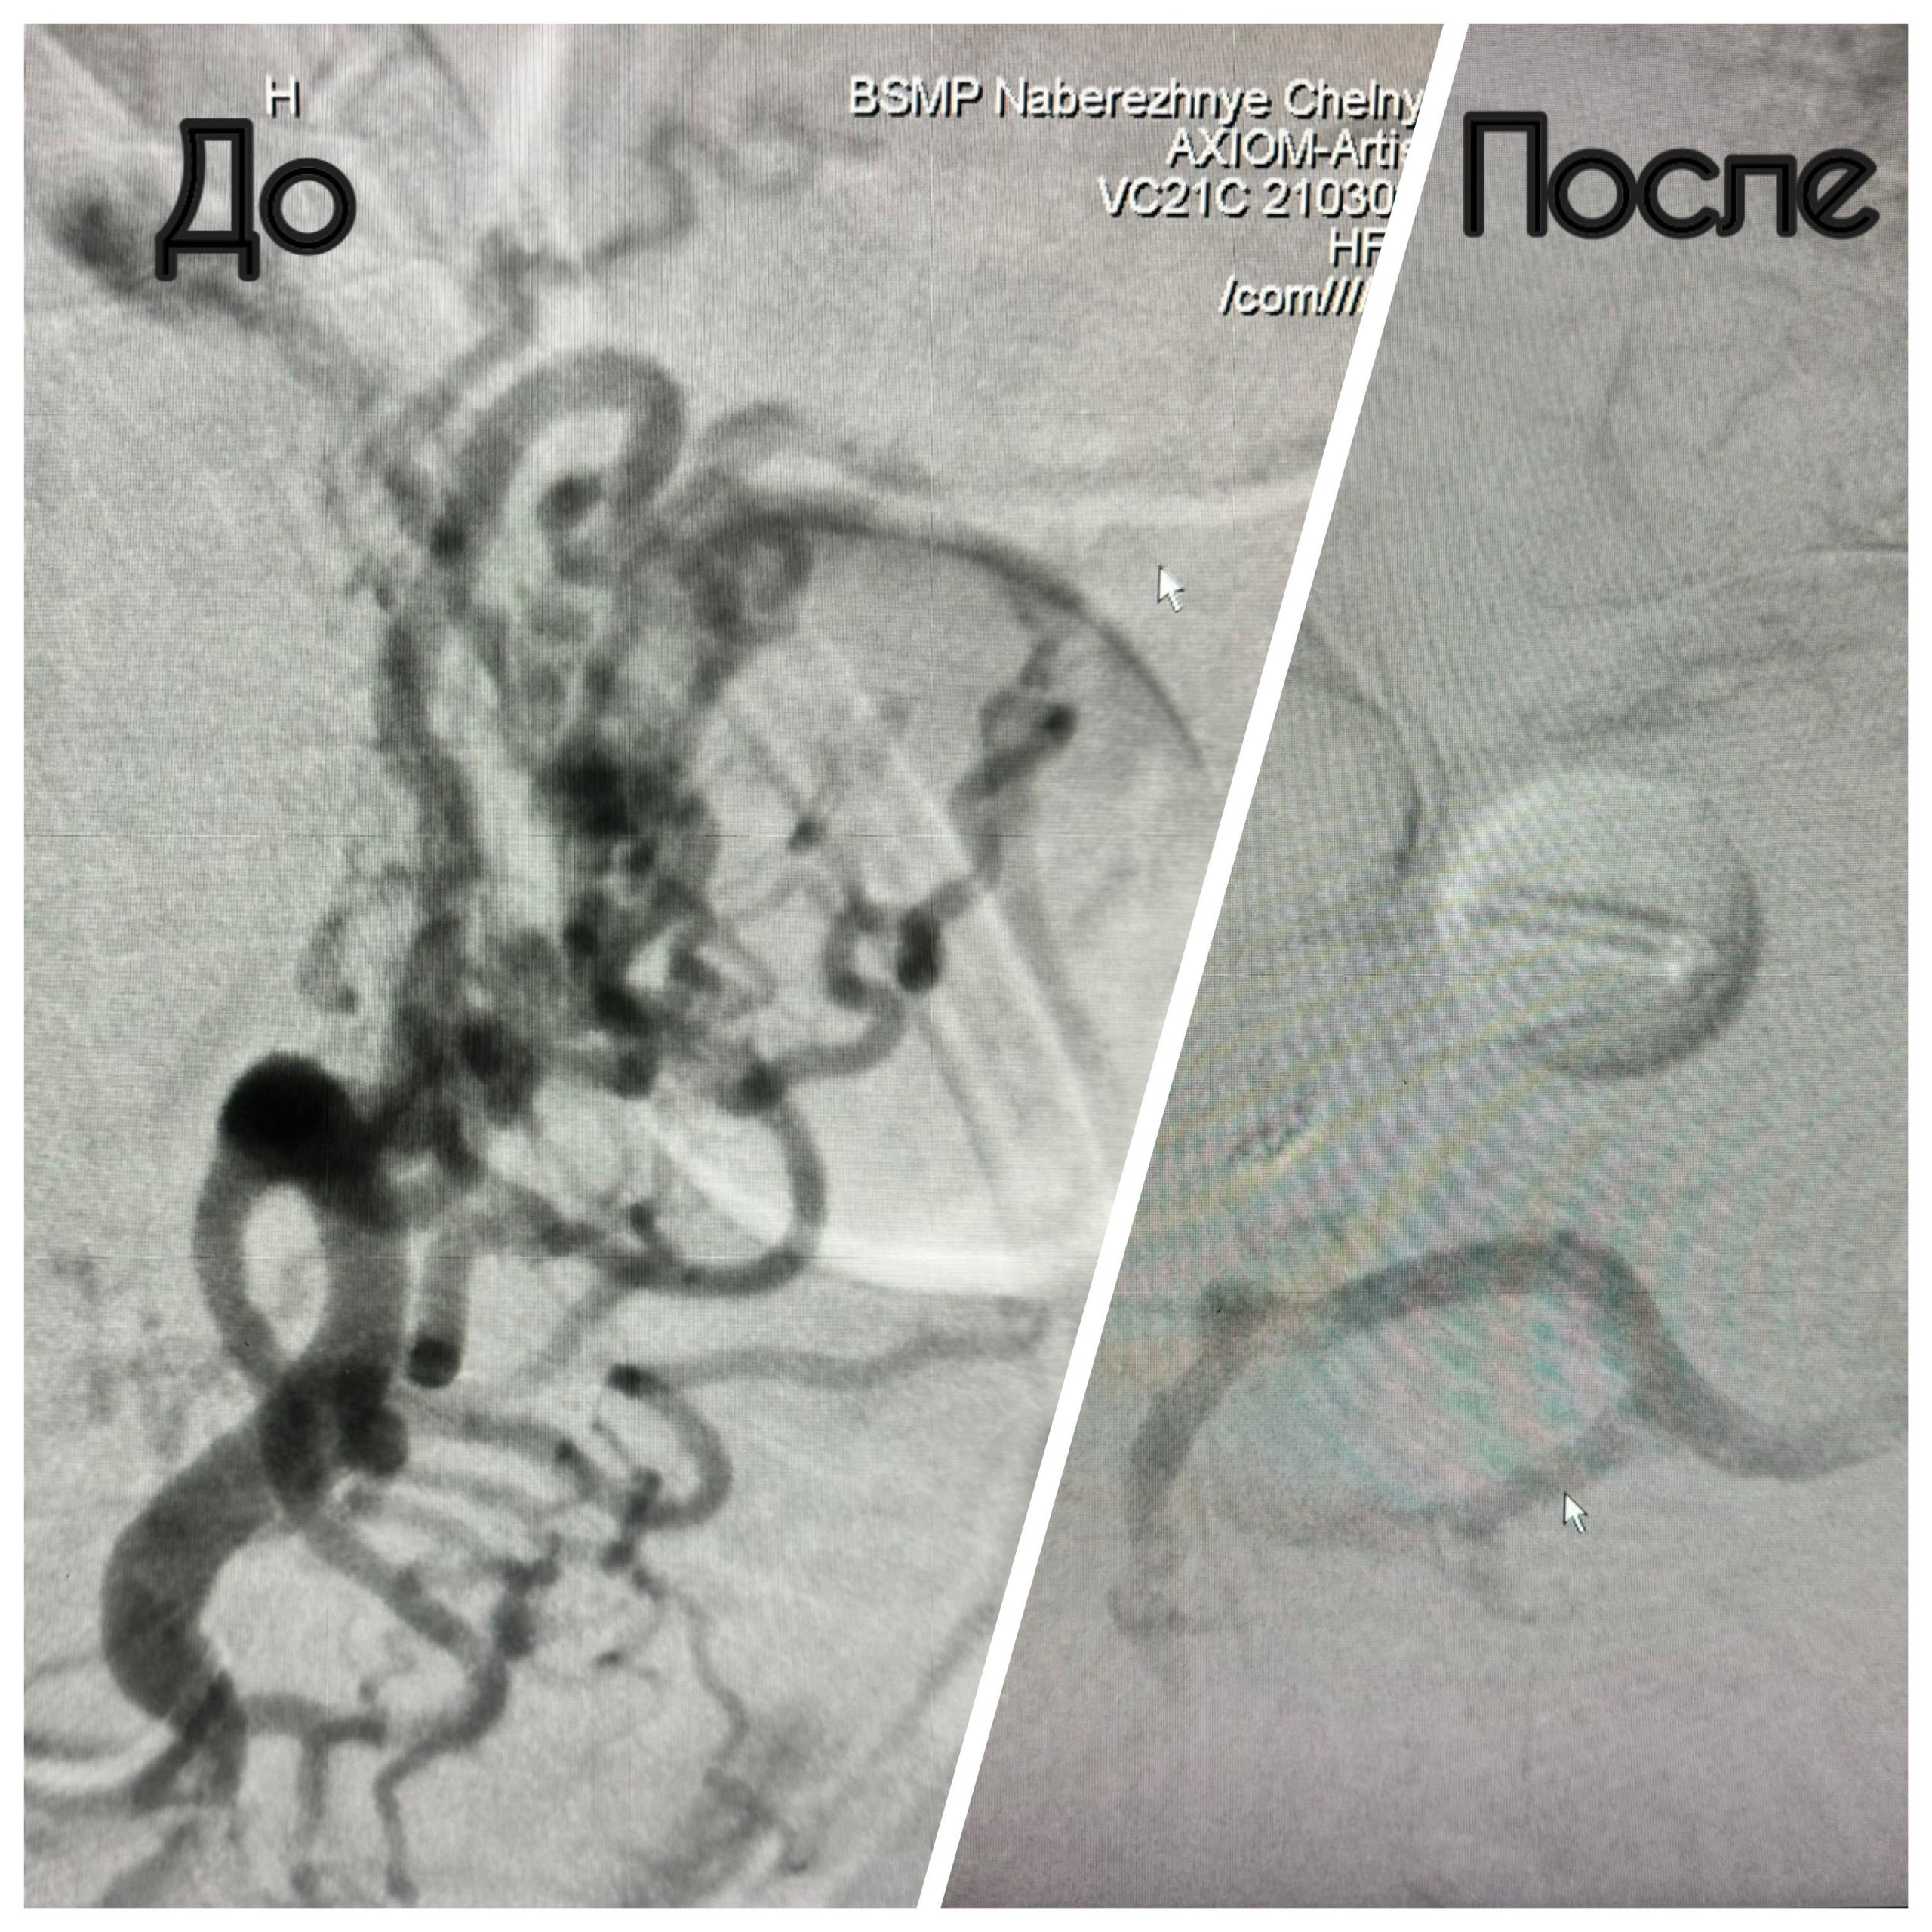

В Набережных Челнах хирурги БСМП провели редкую операцию мужчине с пораженной печенью. Диагноз, с которым поступил пациент – тромбоз ветвей воротной вены, осложненный внутренним кровотечением. Это тяжелое заболевание, при котором кровеносные сосуды печени закупорены, и кровь пытается найти выход, накапливаясь в других сосудах. Как правило, в пищеводе и, в частности, в желудке.В результате возникает варикозное расширение вен и массивное профузное кровотечение. В данном случае пациенту остается только ждать пересадку печени. По словам заведующего отделением рентгенохирургических методов диагностики и лечения №2 БСМП Марата Шарафутдинова, раньше при таких случаях люди не доживали до трансплантации.

Первым этапом врачи по обходным путям закрыли варикозное расширение вен желудка, затем соединили сосуды. Операция проводилась эндоваскулярным способом, через два прокола диаметром 2,5 мм – в правом боку и бедре.